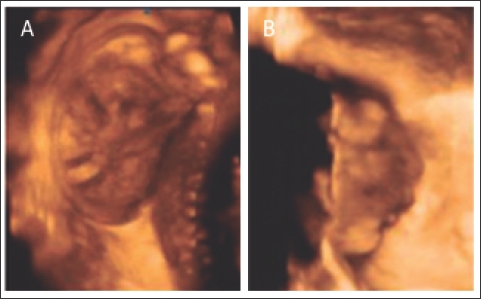

El diagnóstico confirmado mediante ultrasonografía 3D (fig. 2, A y B).

Figura 2. Ecografía 3D. A Masa encefálica libre y columna cervical normal; B Perfil de cara, con ausencia de calota.